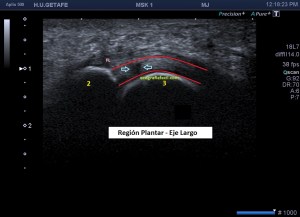

Para mi entender la anatomía me resultó vital, para luego poder correlacionar con la ecoarquitectura…en la imagen 1 puedes ver un dibujo, lo siento, no soy Monet como muy bien puedes comprobar, pero espero que te sirva para que entiendas como es la anatomía, superbásica, de un corte sagital de una metatarsiano en la articulación de la cabeza del metatarsiano (3) con la falange proximal (2) y su relación con la placa plantar (1), en rojo, el tendón flexor del dedo que estemos estudiando (5), en rosa, y la vaina que lo rodea (4), en azul…imposible olvidarme del verde, es la fascia plantar y es el número 6.

Aprendí que para estudiar una lesión debes conocer la mecánica de la lesión, en este caso, es una hiper extensión de la articulación que hace que la placa plantar estire demasiado y se pueda llegar a romper, lo que puede provocar líquido en la zona. Es una típica lesión de bailarinas, deportistas en general y personas que usan tacones muy pronunciados en sus zapatos. Te dejo la imagen número 2, donde puedes ver el teórico foco de una lesión marcada con una estrellas de 5 puntas como la de mi escudo.

Anatómicamente la placa plantar es una estructura fibrocartilaginosa altamente resistente debido al colágeno tipo 1. Ecográficamente, está entre el flexor del dedo y la cabeza del metatarsiano y su aspecto es hiperecogénico, ocupando el espacio que va desde el cuello del metatarsiano hasta la porción distal y plantar de la falange articular con el metatarsiano. Imagen 3 y 4, normalidad ecográfica. Imagen 5, imagen patológica.

Si sabemos que la estructura es de una intensidad ecogénica alta, la aparición de focos hipoecogénicos en el lugar pueden ser constitutivos de lesión locoregional, temerosos siempre de la anisotropía, aunque no es una anatomía tendinosa, la colocación de la sonda no es fácil por la orografía de la zona y por tanto, siempre con las orejas de punta…y gel, usamos mucho gel para que el apoyo sea perfecto. Te he dicho anteriormente que la rotura de esta estructura puede acarrear a presencia de líquido que se verá anecoico en la zona.

Estudiamos y demostramos la lesión o la normalidad en dos proyecciones, imagen 6, eje largo y eje corto de la zona y podemos comparar siempre con el lado contralateral, previsiblemente sano, dicho todo este conglomerado de ideas…las imágenes:

3

4

5

6

Marcadas con flecha azul puedes ver un efecto de discontinuidad a nivel de la placa plantar, hipoecogénico e irregular, demostrado en dos proyecciones.